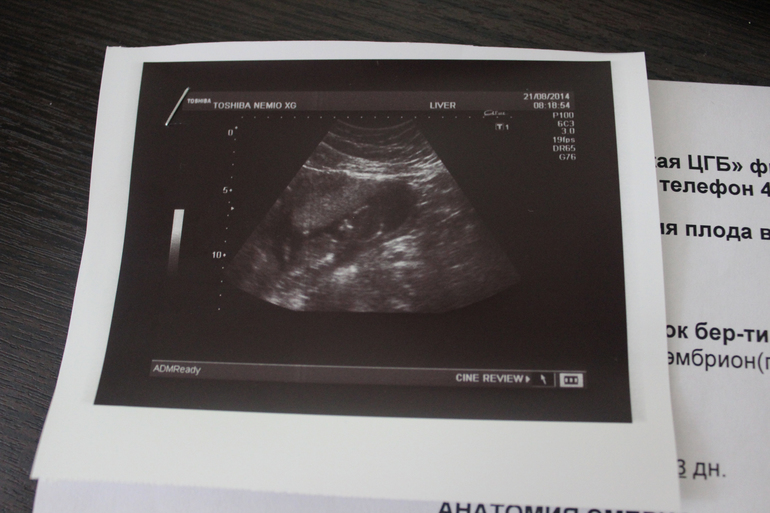

Долгожданное УЗИ!!!

Результаты:

КТР- 78 мм( ничего себе вымахал, не зря я ему шведский стол устраивала, ела все подряд по немногу

Сердцебиение определяется( А частоту измеряют попозже??) Там ничего не написано=((

Размеры плода соответствуют 14 нед и 3 дня

Воротниковая зона 1,8

Носовая кость(соответствует сроку беременности)(а почему нет размера?)

Конечности без видимых потологий

Аномалии выявляемые на данном сроке не обнаружены

Хорион по передней стенке(это уже 3й раз мне говорят, пиночков еще долго не видать мне)

Околоплодные воды-нормальное кол-во вод

Длина шейки матки 3 см( не мало???)